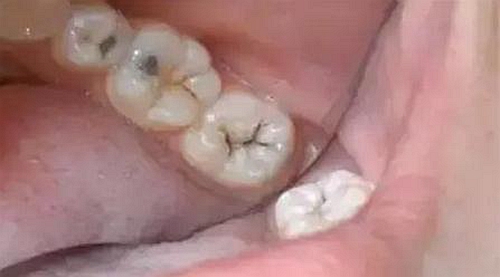

第一步:淺齲

當我們身上有小黑點時,您毫不在意地說:“沒事的,沒感覺。”

牙醫(yī)說:“齲病是由以細菌為主的多因素導致的牙齒硬組織發(fā)生慢性進行性破壞的一種疾病。已經(jīng)開始淺齲即牙釉質(zhì)齲,需要做藥物治療或充填治療。